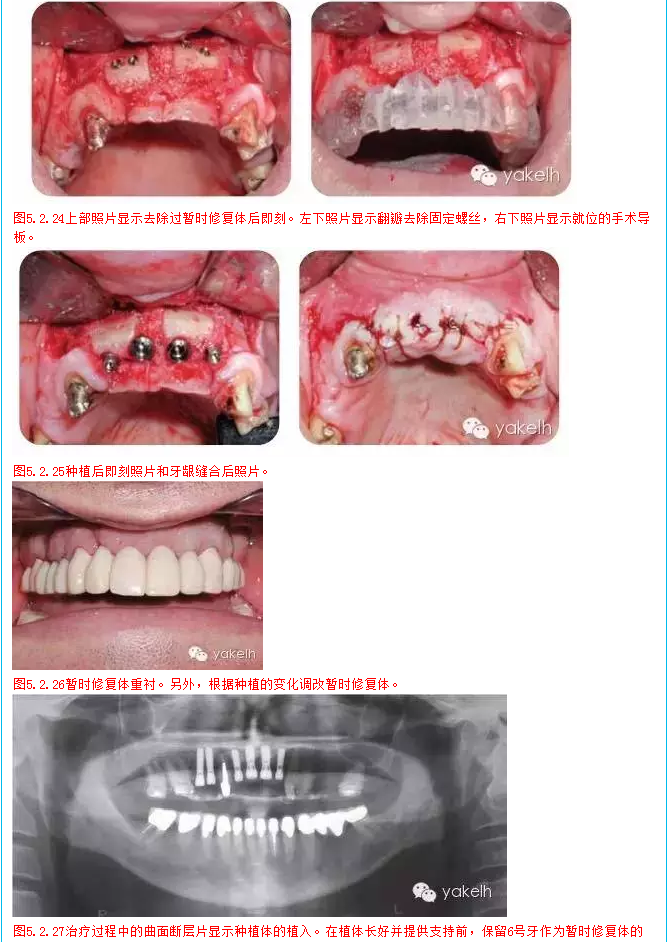

¤¤因關(guān)鍵基牙遠(yuǎn)期預(yù)后較差,臨床上經(jīng)常需要將牙支持式固定橋換成種植體支持式固定橋。治療的困難在于整個(gè)治療過程中因?yàn)榛颊卟荒芙邮芑顒?dòng)的暫時(shí)修復(fù)體,需要制作固定的暫時(shí)修復(fù)體。該患者在其他國家進(jìn)行了整個(gè)牙合重建。但對(duì)結(jié)果不滿意,也不喜歡美學(xué)效果,上唇過于凹陷,咬合也不舒適。此外,修復(fù)體結(jié)構(gòu)和邊緣適合也不足,需要全部更換。部分牙齒缺失,并且關(guān)鍵基牙—右上尖牙,遠(yuǎn)期預(yù)后差。因此,治療計(jì)劃包括植骨在內(nèi)的口腔種植手術(shù)。

1  在2天內(nèi)分2次全牙列暫時(shí)性修復(fù)

2  種植區(qū)口腔外科骨移植手術(shù)

3  調(diào)整和修改暫時(shí)修復(fù)體

7  待種植后愈合和骨整合,調(diào)整和維護(hù)暫時(shí)修復(fù)體

8  安置種植體基臺(tái),拔除6號(hào)牙,制作種植體支持式暫時(shí)修復(fù)體

9  拔牙創(chuàng)愈合

10  最終的上頜修復(fù)體,2,3號(hào)牙為單獨(dú)修復(fù),4號(hào)至10號(hào)牙為種植固定橋,6號(hào)牙為橋體,11號(hào)至15號(hào)牙為牙支持式固定橋